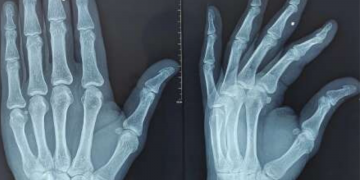

Nueva enfermedad descubierta: “Síndrome de dolor del medio Oriente”.

Médicos han documentado cientos de pacientes con lo que ellos han denominado como «síndrome de dolor del Medio Oriente», enfermedad … Sigue leyendo Nueva enfermedad descubierta: “Síndrome de dolor del medio Oriente”.